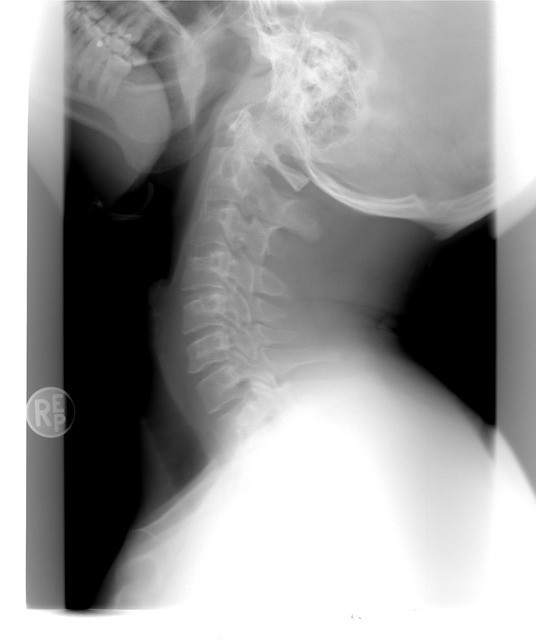

목디스크가 의심되면 진단법을 이용해서 직접 판단해볼 수 있다. 가장 먼저 디스크가 있으면 손가락에 감각이 떨어져서 섬세함도 없어진다. 그러므로 글씨 쓰기가 힘들거나 단추 잠그는 게 어려우면 목디스크를 의심해야 한다. 젓가락질도 잘 못하고 동그라미가 똑바로 그려지지 않으면 목디스크를 의심해야 한다. 또한 디스크가 생기면 목과 팔의 신경을 압박하면서 어깨와 손이 저릴 수 있다. 어깨와 손에 났던 쥐가 양 팔을 들어올렸을 때 통증이 나아진다면 디스크의 영향일 수 있다. 목디스크 환자들이 실제로 병원을 방문할 시 팔을 머리위로 올려서 진료실에 온다고 한다. 또 목 디스크가 오면 힘이 약해져서 손가락의 마디 한개마다 힘이 빠지게 된다. 그러므로 손가락을 붙이면 대략 20초 안으로 멀어지게 된다. 또 하체 기능 감소로 걸을 때 휘청거리게 된다. 더 자세히 판단하고 싶으면 바닥에 일직선을 그린 다음 밟으면서 걸어가보면 된다. 똑바로 걷지 못할 경우 목디스크의 가능성이 있다.